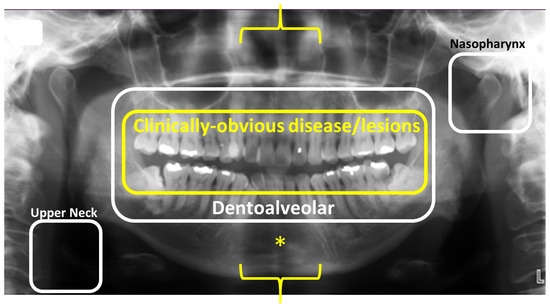

5. Dental Panoramic Radiography—Revisited

- MacDonald, D.; Yu, W. Incidental findings in a consecutive series of digital panoramic radiographs. Imaging Sci. Dent. 2020, 50, 53–64. [Google Scholar] [CrossRef] [PubMed]

- MacDonald, D.S.; Martin, M.A.; Wu, J.S. The responsibility of dentists in radiologic examination of the nasopharynx. Oral Surg. Oral Med. Oral Pathol. Oral Radiol. 2024, 137, 441–445. [Google Scholar] [CrossRef]